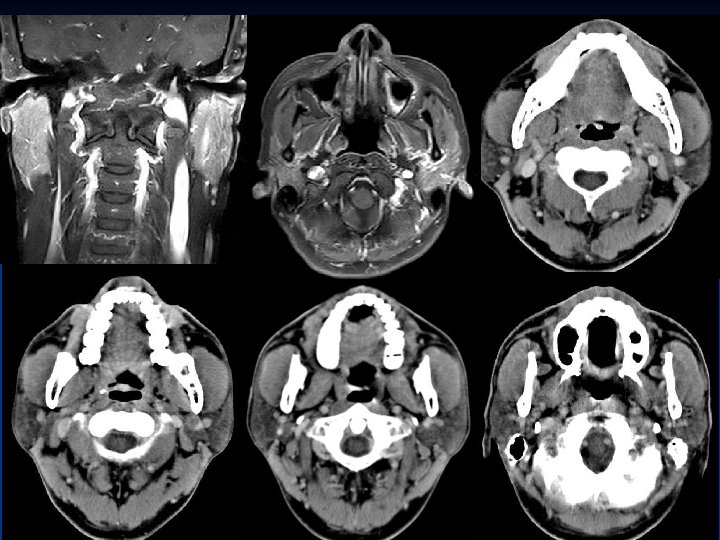

Nasopharynx n Keywords: -- Rosenmüller fossa, Torus tubarius , Eustachian tube orifice -- Pterygopalatine fossa (PPF) -- Parapharyngeal space (PPS) -- Retropharyngeal space (RPS) -- Prevertebral musculature -- Foramen lacerum-ICA (perivascular), -- Foramen ovale-V 3 (perineural)

Parapharyngeal space (PPS) n n Fat Branches of cranial nerve V 3 Ascending pharyngeal artery Pharyngeal venous plexus

Retropharyngeal space (RPS) Fat n Lateral retropharyngeal nodes (of Rouviere) n Medial retropharyngeal nodes n

Prevertebral musculature

Foramen lacerum-ICA

Foramen ovale-CN V 3 Foramen lacerum-ICA Foramen lacerum Foramen ovale